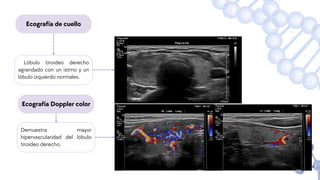

Ecografía de cuello

Lóbulo tiroideo derecho

agrandado con un istmo y un

lóbulo izquierdo normales.

Demuestra mayor

hipervascularidad del lóbulo

tiroideo derecho.

Ecografía Doppler color